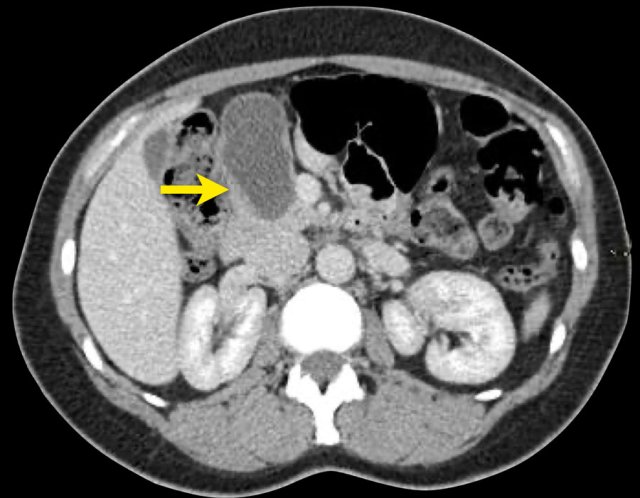

CT-images of a 32 year-old female with pain in the upper left quadrant radiating to the back.

There is a large cyst in the pancreatic tail with peripheral calcification.

There is subtle septation as seen on the left image and wall thickening.

You may have to enlarge the image to see the septation.

A specific diagnosis of a MCN can be made.

CT-image of a 46 year old female with vague right abdominal complaints.

The imaging findings are:

- septated cyst of 7 cm in the pancreatic head.

- smooth capsule.

- no lobulation.

- no connection to the pancreatic duct.

MRI revealed a septated pancreatic head cyst of 7 cm with a smooth capsule without lobulation and no connection to the pancreatic duct.

Surgery showed a low grade mucinous cystadenoma with ovarian stroma.